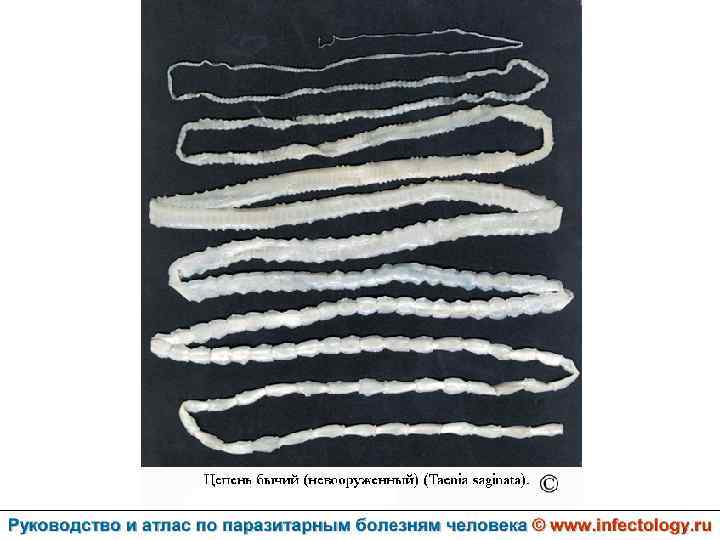

Тениаринхоз (шифр по МКБ 10 - B 68. 1) – антропонозный биогельминтоз с хроническим течением, характеризующийся преимущественно желудочно– кишечными расстройствами.